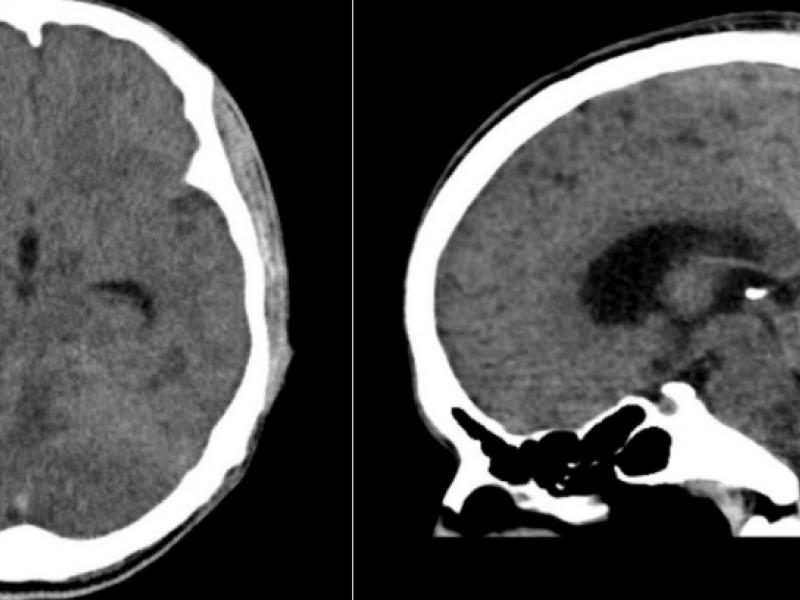

What's the diagnosis?  By Dr. Katie Nowlan

February 17 2021

A 26 yo male is brought in with a change in mental status